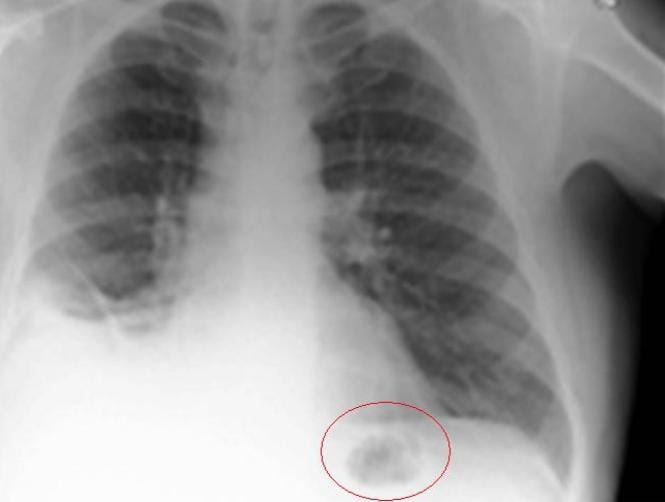

A scan to determine the cause of his symptoms showed that he had a shadow in his lung.

However, tests at the Royal Preston Hospital revealed that the mass was a traffic cone from a Playmobil set, according to BMJ Case Reports. This prompted the man to recall that he had received a Playmobil set on his seventh birthday.